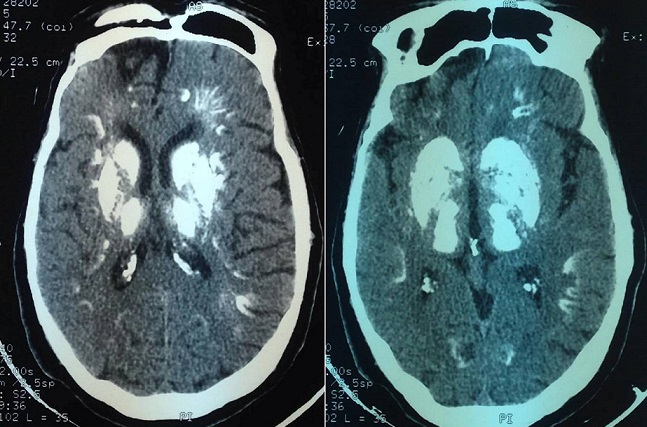

Le syndrome de Fahr (SF) est caractérisé par la présence de calcifications intracérébrales, bilatérales et symétriques, des noyaux gris centraux. Il est souvent associé à des troubles du métabolisme phosphocalcique, et principalement à une hypoparathyroïdie. Il constitue une complication rare de la radiothérapie probablement lié à une vascularite nécrotique. Nous rapportons l'observation d'un homme âgé de 27 ans qui était hospitalisé pour syndrome dysmorphique acrofacial. Le diagnostic d'une acromégalie secondaire à un macroadénome hypophysaire a été retenu. Une première exérèse fut réalisée, suivie de d'une réintervention pour récidive et d'une radiothérapie complémentaire de 56 grays répartis sur 12 séances. L'évolution était marquée par la survenue d'une insuffisance antéhypophysaire. Cinq ans plus tard, le patient présentait des céphalées frontales. Un scanner cérébral objectivait un aspect stable de la tumeur, par ailleurs, elle révélait une calcification quasitotale des noyaux gris centraux, du tronc cérébral et du cervelet, de la substance blanche et de la jonction cortico-souscorticale absentes sur les examens neuroradiologiques précédents. Le diagnostic d'un syndrome de Fahr a été porté. Le bilan biologique ne révélait pas de troubles du métabolisme calcique, ni d'hypoparathyroidie. L'hypothroidie et l'hypogonadisme ont été incriminés mais le caractère étendu des macrocalcifications n'était pas en faveur. Ainsi, l'origine post radique était retenue. Une surveillance clinique rapprochée était préconisée afin de déceler d'éventuelles complications neurologiques.